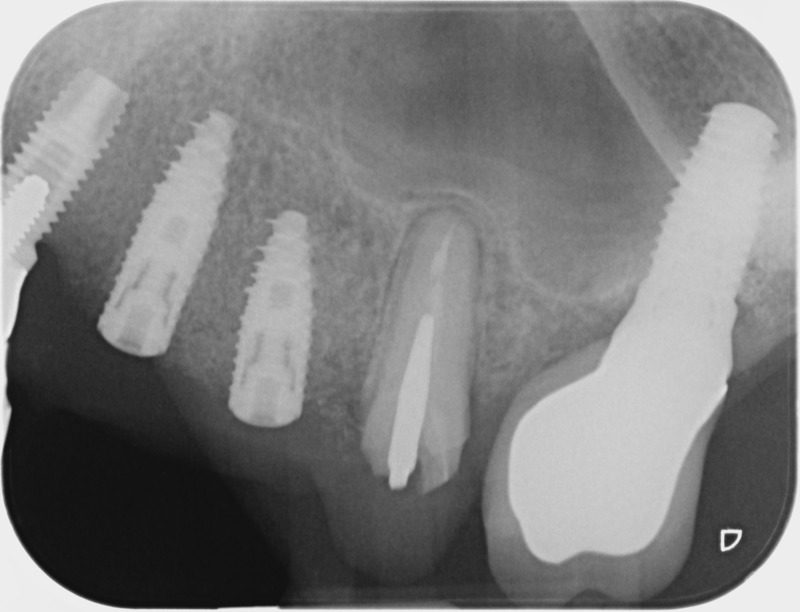

• Couronnes sur implants : Lorsqu’un implant est posé en remplacement des racines d’une dent, il est conçu pour recevoir d’abord un pilier vissé puis une couronne céramique. Le couple couronne - implant se substitue à la dent manquante pour en assurer les mêmes fonctions. Nous pouvons également adapter un bridge sur plusieurs implants dans le cas d’un édentement plus important.

Avant

Après